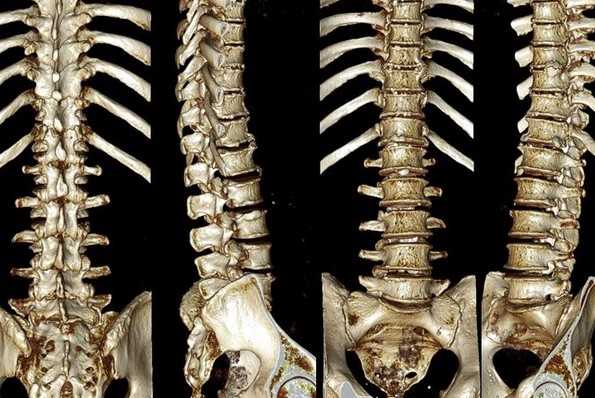

Патогномоничные признаки синдрома Лобштейна

- Генерализованный остеопороз

- Множественные старые переломы

- Искривление костей

- Множественные «рыбьи» позвонки.

- Переломы тела позвонка (трансформация тел позвонков в так называемые «рыбьи» позвонки в поясничном отделе и клиновидные позвонки в грудном отделе позвоночника)

- Кифосколиоз (из-за слабости связочного аппарата)